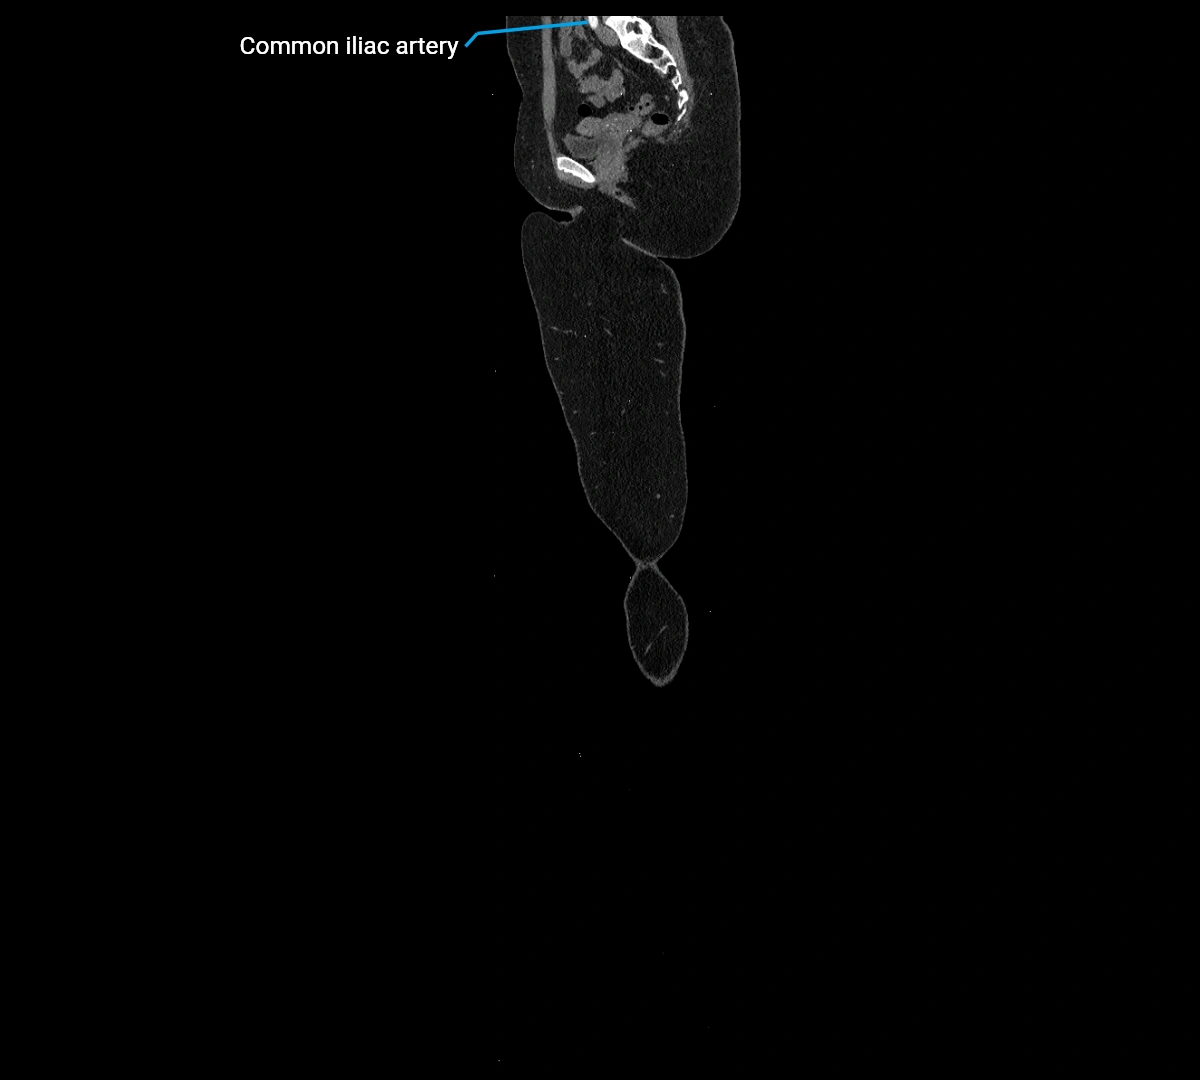

MRI images

image